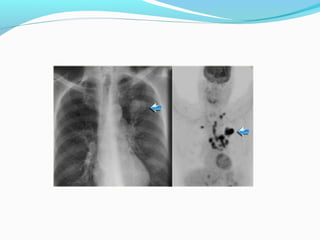

CALCIFICATION

FDG UPTAKE

STAGE ??